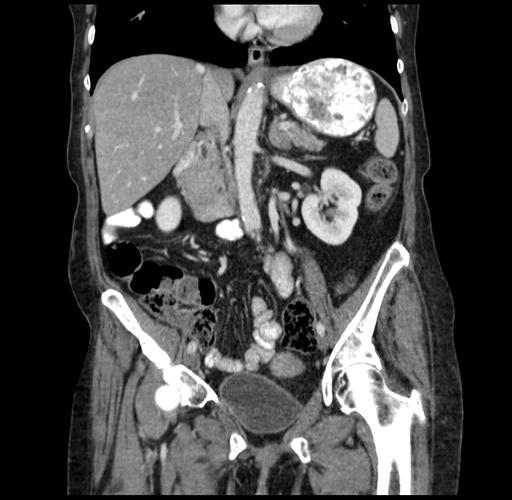

Pre-Chemo: Coronal Venous

Coronal Venous